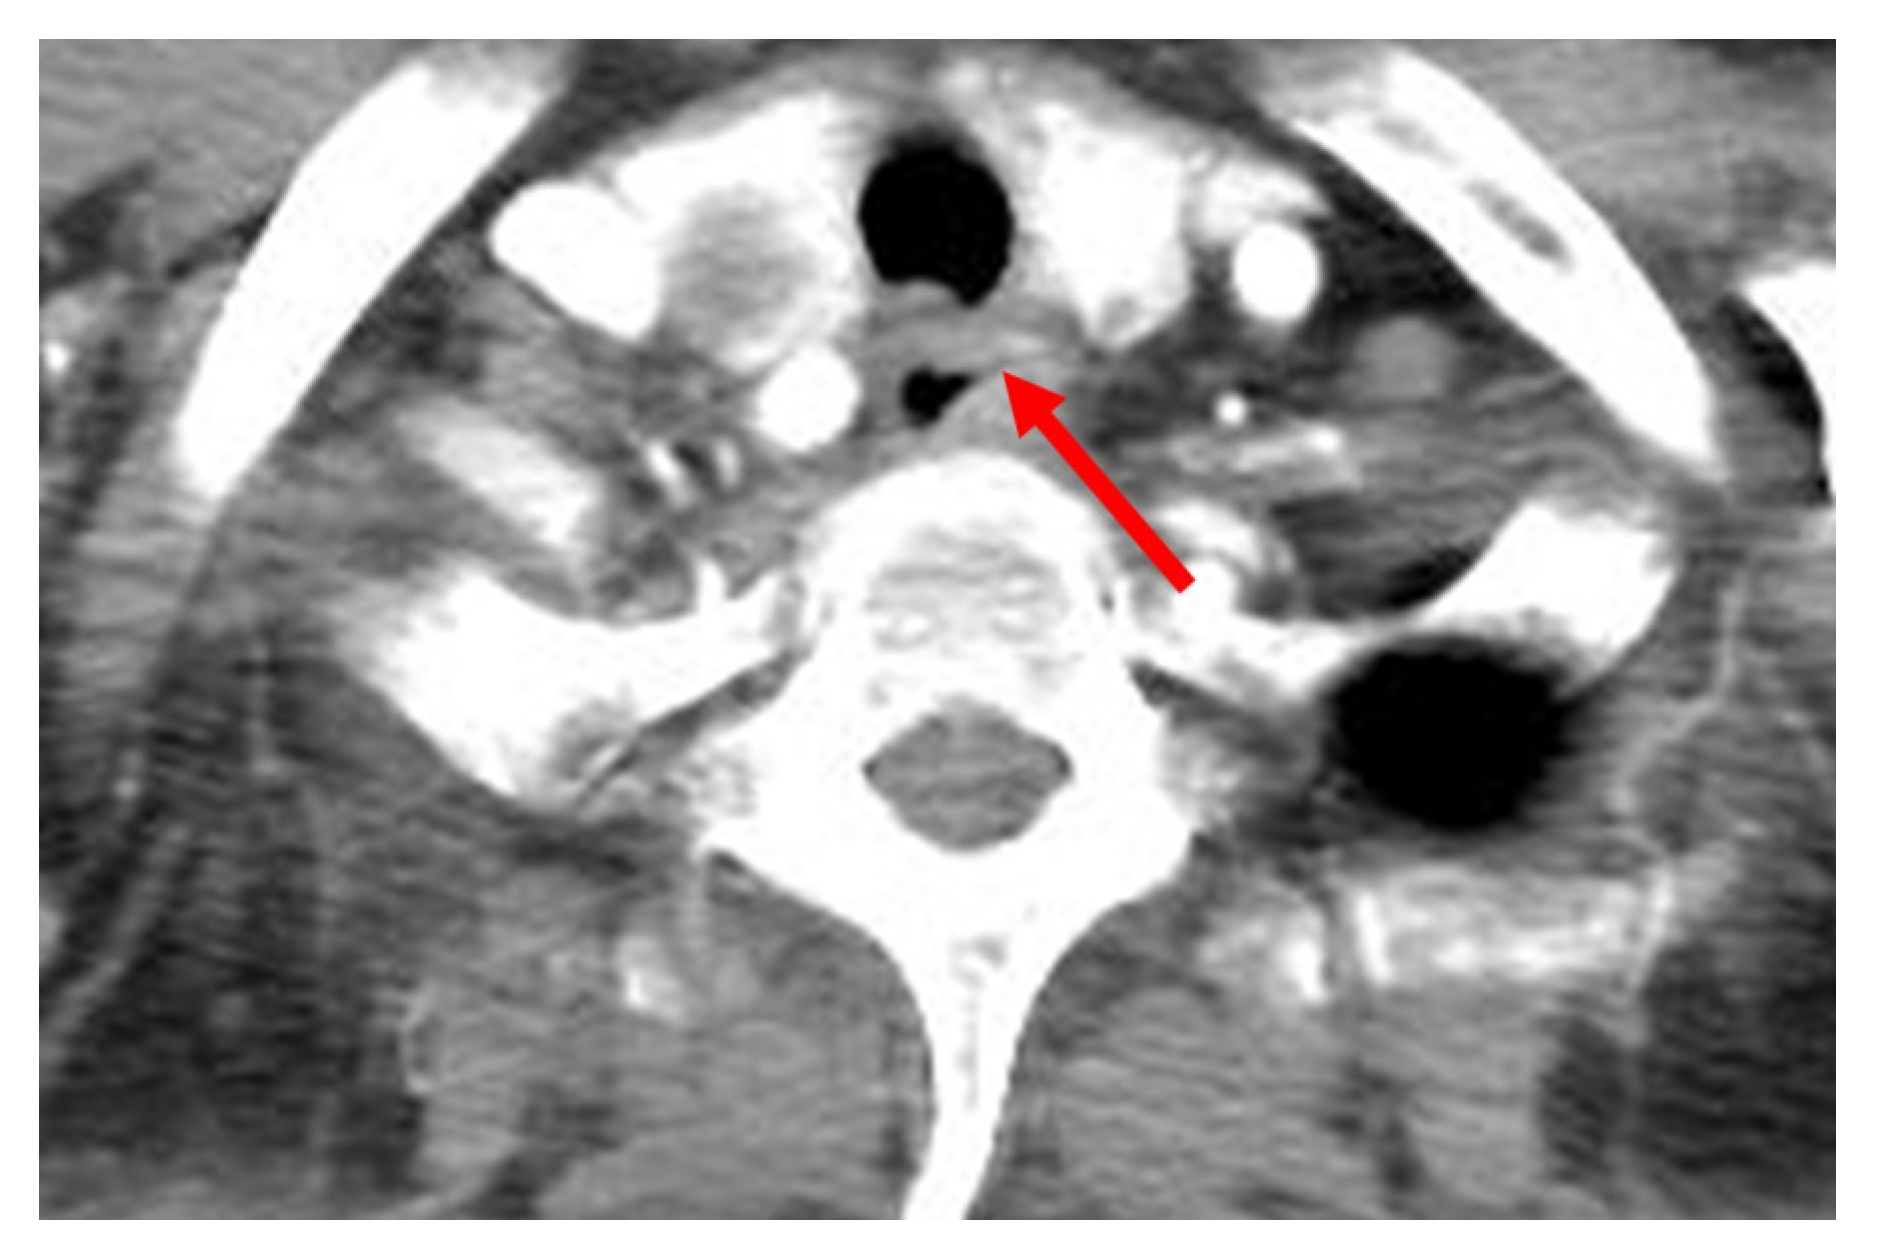

2. Detailed Case Description